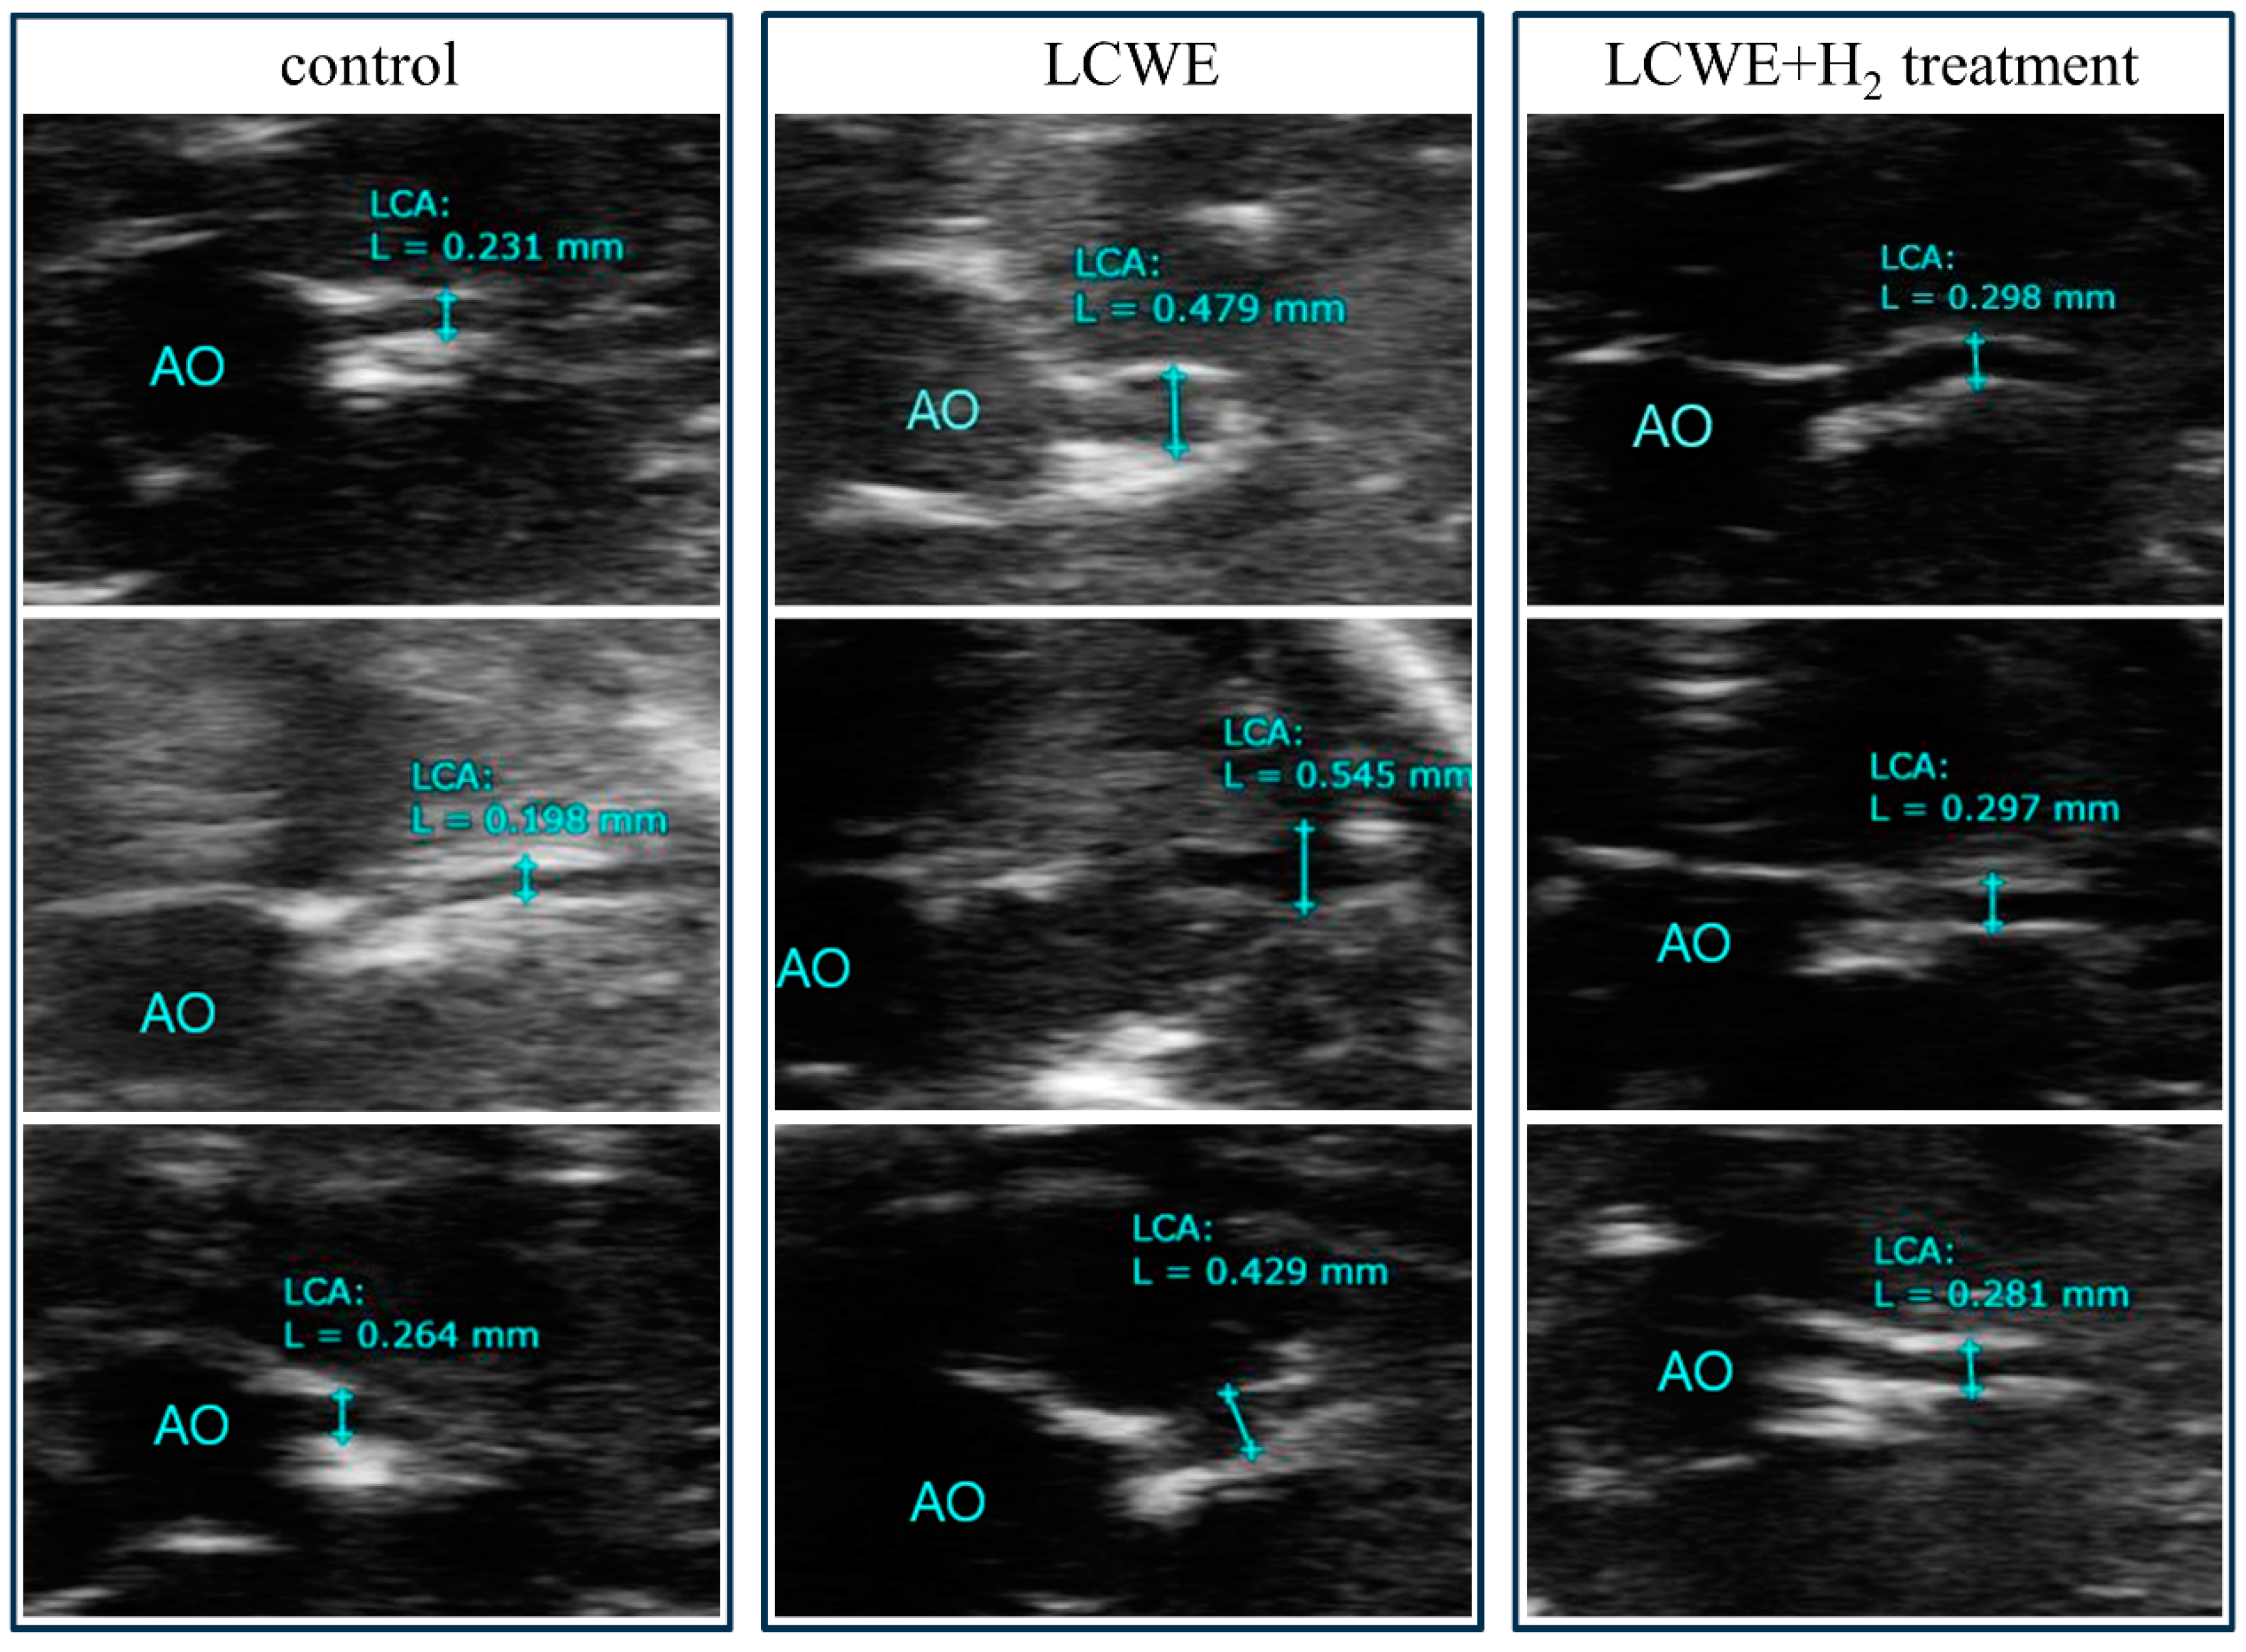

3.1. Resolution of Dilatation of CALs in LCWE-Injected Mouse Model Following Treatment with Inhaled Hydrogen Gas